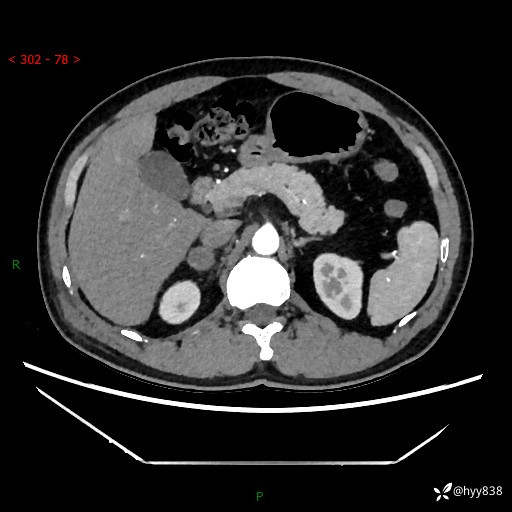

现病史:患者9月4日摔伤在深圳市宝安区中心医院行CT检查提示右侧肾上腺区结节(38*27mm),复查B超提示右侧肾上腺区可见一61*24mm异常低回声团,建议进一步检查。进一步完善增强CT后提示:右侧肾上腺区肿块及周围渗出改变,大致同前,考虑肾上腺腺瘤,不除外瘤内出血可能,否认阵发性头晕、头痛、出汗、乏力等不适,门诊以“ 右侧肾上腺肿瘤”收入住院。 起病来,患者精神、食欲、睡眠可,大便通畅,小便如上述,体力体重无明显改变。

肾上腺CT平扫

增强(动脉期+静脉期)